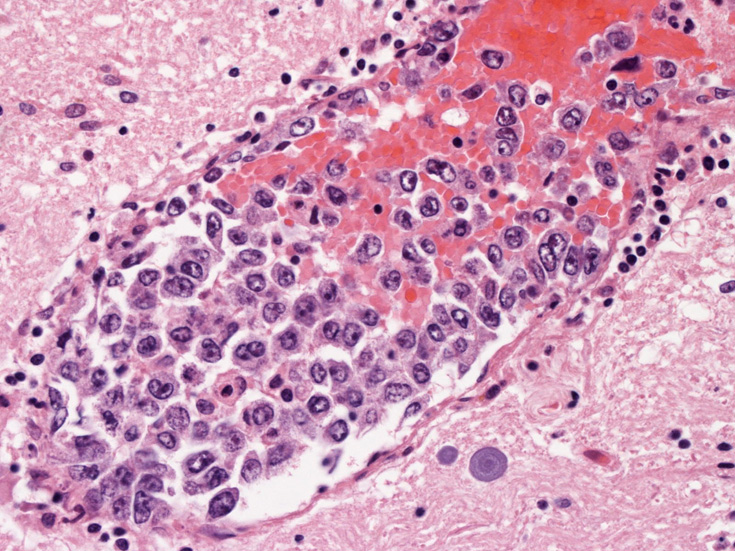

脳;くも膜下腔の小動脈内, 脳白質の細血管内に腫瘍細胞が充満している。

CD20陽性大型リンパ球の血管内増殖; 血管内増殖細胞はCD20陽性。

血管腔内に選択的に悪性リンパ腫細胞が増殖することを特徴とする節外性large B-cell lymphomaのまれなタイプ。WHOの定義ではBリンパ球の腫瘍であること, 血管内に腫瘍細胞が限局していることを診断の要件としている。歴史的には血管内皮の腫瘍性増殖とされneoplastic angioendotheliomatosisという用語が使用されてきたが, 1985年Moriらが免疫組織学的手法により増殖細胞がリンパ球あることを明らかにした*1

生検組織により血管内腔を塞ぐように大型異型リンパ球が増殖していることを確認することが診断の要件である。血管内増殖の病変分布が本病型では, 脳, 肺, 肝, 腎, 副腎, 皮膚, 骨髄など特有である。しかし大細胞型B細胞リンパ腫にはこのような臓器を選択的に侵襲するが, 血管内腔には増殖しないものがあることに留意が必要である。